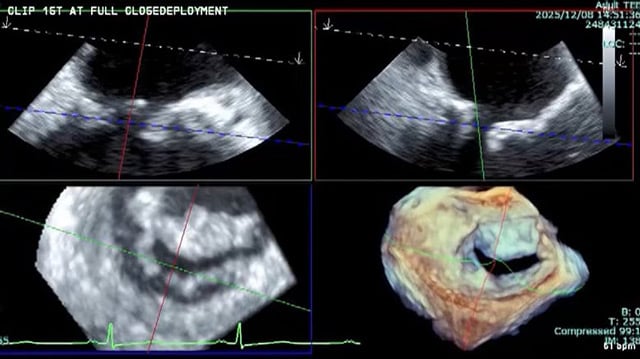

Mitral TEER masterclass

14 Feb 2026 – From PCR Tokyo Valves 2026

Delve into the mitral TEER masterclass focusing on unique anatomical challenges encountered in Asian populations. This session presents complex case studies illustrating device strategies and practical techniques aimed at minimizing complications and optimizing procedural outcomes in anatomically challenging scenarios.